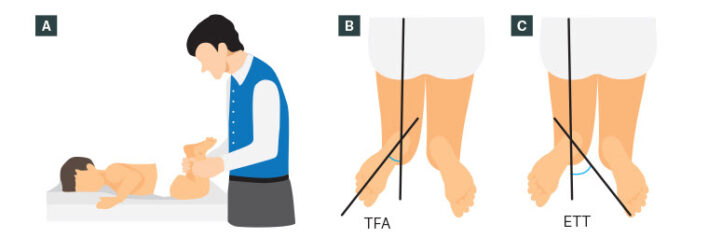

Xoay ở háng (đùi) thường được đánh giá với bệnh nhi ở tư thế nằm sấp, háng duỗi và gối gập đến 90°. Đánh giá tầm xoay trong và xoay ngoài của khớp háng. Gia tăng xoay trong khớp háng biểu hiện vặn trước của xương đùi, ngược lại tăng xoay ngoài có thể là biểu hiện của vặn sau và đụng chạm xương đùi – ổ cối. Để xác định mức vặn ra trước của xương đùi có thể đánh giá test Craig: đo góc giữa xương chày và trục đứng dọc vuông góc với mặt giường. Góc này ở người bình thường khoảng 15 độ.

Xoay của xương chày thể hiện qua mối tương quan giữa đường liên hai mắt cá (transmalleolar axis) với với trục dọc của đùi. Có thể đánh giá điều này thông qua đo trục đùi -bàn chân (trục đùi- bàn chân cũng thay đổi khi có sự xoay của phần bàn chân sau, hind foot). Trẻ nhũ nhi thường có góc đùi- bàn chân xoay trong 5° và chuyển sang xoay ngoài khoảng 10° lúc trẻ 8 tuổi. Cũng có thể đo góc đường giữa trục xương đùi với đường liên mắt cá.